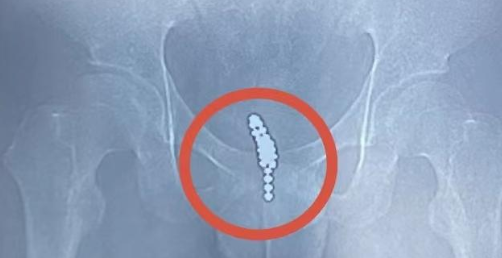

术前检查可见,膀胱内有串珠样异物

家人立即将他送往附近医院,通过泌尿系CT检查发现,膀胱内有一团串珠样异物。医生表示,由于磁力珠数量多、磁力极大,无法经尿道取出,将膀胱切开才能将异物取尽。得知开刀会在下腹部留下一道长长的手术疤痕,且术后恢复时间较长、感染风险较高之后,小叶和家人希望寻求创伤更小、恢复更快的微创手术方式,于是当天下午来到湖南省人民医院泌尿外科向旻主治医师处就诊,随即以"膀胱异物"收入泌尿外科二病区住院。